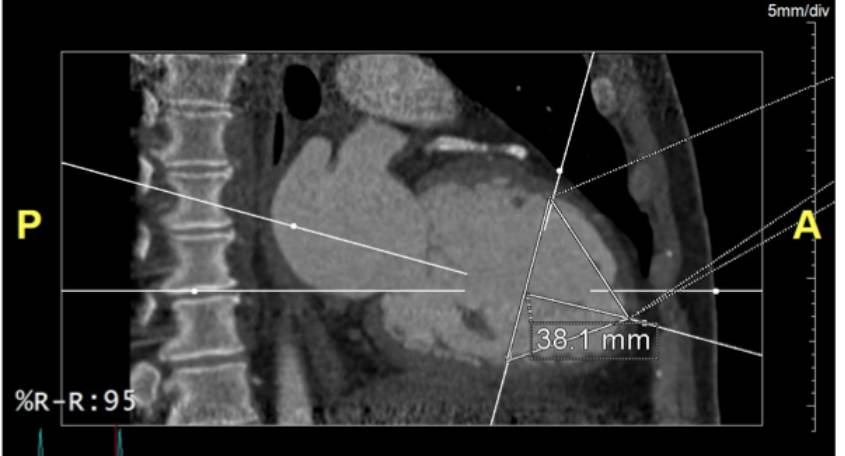

Patient selection-CT:

Height from the apx to implant landing zone: 38.1mm